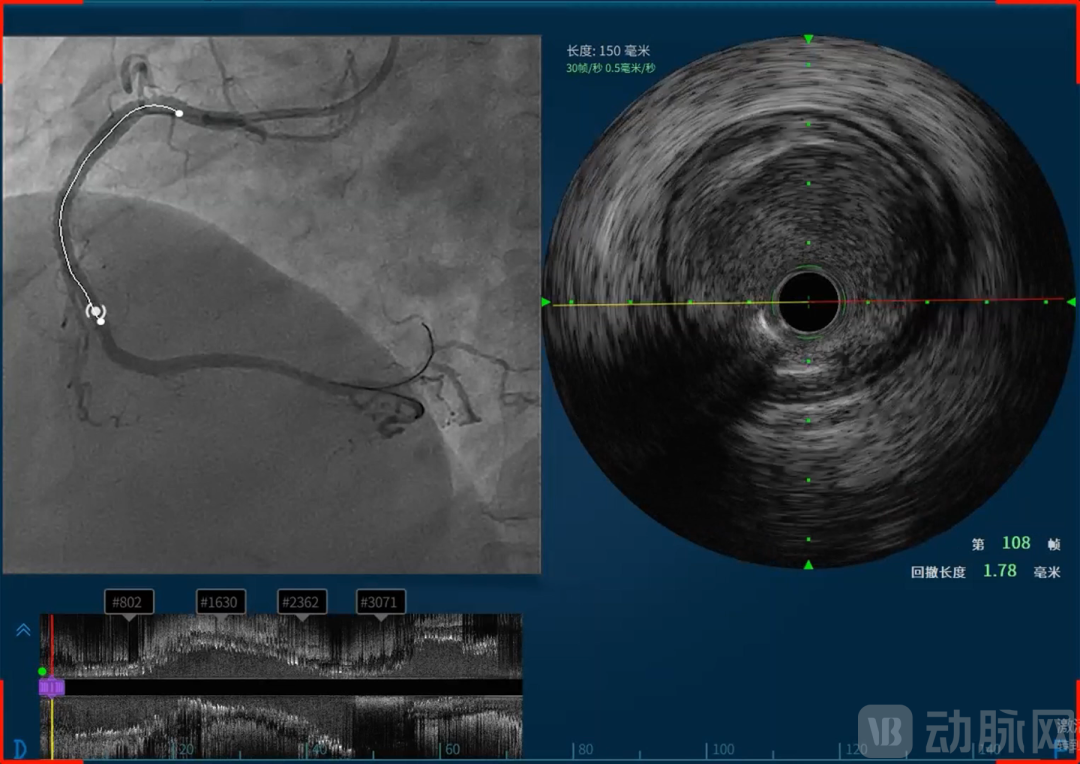

价值内核,构建国内稀缺血管介入诊疗一体化平台

恒宇医疗的吸引力不仅在于所深耕的血管介入赛道,更在于其致力于构建的完整技术体系和难以复制的研发能力。恒宇医疗深耕血管内超声(IVUS)和光学相干断层成像(OCT)技术领域多年,形成了从核心元器件到整机设备,从单一产品到系统解决方案的全链条布局。恒宇医疗是国内少数同时掌握IVUS和OCT两项核心技术的企业,这种“双技术路线”并行的能力使其在血管介入精准诊疗领域占据了独特位置。同时融合OCT与近红外光谱(Near-Infrared Spectroscopy, NIRS)的单光源双模态OCT-NIRS技术的成功,更使恒宇医疗成功建立了OCT/IVUS/NIRS三模态成像模式,为临床诊疗提供了更为全面的解决方案。

天津恒宇医疗成立于2016年,专注于血管内超声(Intravascular Ultrasound, IVUS)设备及导管、光学相干断层成像(Optical Coherence Tomography, OCT)设备及导管、IVUS/OCT一体机式的双导管系统、基于IVUS和OCT的无创血流储备分数(Fractional Flow Reserve, FFR)平台、融合OCT与近红外光谱(Near-Infrared Spectroscopy, NIRS)的单光源双模态OCT-NIRS技术及血管内激光斑块消蚀技术的自主研发、生产和销售,掌握光学、超声及导管平台技术,并不断基于底层技术进行全球领先的创新,致力于为医患提供以影像类产品为基础的泛血管一体化解决方案。